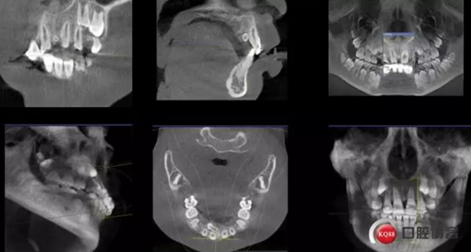

CBCT術前分析,精準找到牙齒的具體位置

確定了方案和術前良好溝通和小孩良好的配合,牙齒很快就拔了出來。